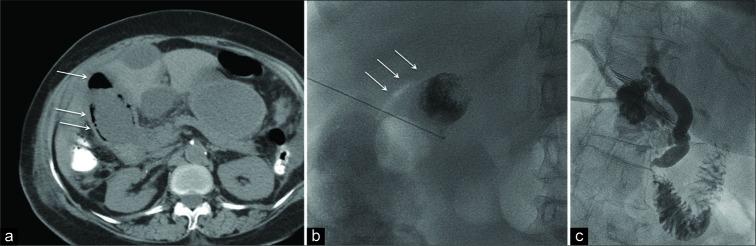

经皮胆囊造瘘术治疗气肿性胆囊炎的安全性和有效性

The objective of the study was to evaluate the safety and efficacy of percutaneous cholecystostomy (PC) in treating critically ill patients with emphysematous cholecystitis who were deemed poor surgical candidates.

Ten consecutive patients were included, with a mean age of 75.0 ± 12.2 years, including six men and four women. The most common comorbidity was diabetes (60%, 6/10) followed by hypertension (40%, 4/10). Intraluminal or intramural gas as well as gallbladder wall thickening were noted in all patients. Procedure technical success rate was 100%. There was a complete resolution of symptoms in 90% (9/10) of patients at a mean of 2.9 ± 1.4 days post-procedure. Thirty-day survival rate was 90% (9/10); one patient died on the 6 post- procedure day from sepsis. Two more deaths occurred within a year after PC from unrelated causes. About 50% (5/10) of patients underwent elective cholecystectomy at a median interval of 69 days post-procedure. In 40% (4/10) of patients, cholecystostomy was the definitive treatment, with tube removal at a median of 140 days post- procedure.

本研究的目的是评估经皮胆囊造瘘术(PC)在治疗被认为手术风险高的重症气肿性胆囊炎患者中的安全性和有效性。

连续纳入10例患者,平均年龄75.0±12.2岁,其中男性6例,女性4例。最常见的合并症是糖尿病(60%,6/10),其次是高血压(40%,4/10)。所有患者均观察到腔内或壁内气体以及胆囊壁增厚。手术技术成功率为100%。90%(9/10)的患者在术后平均2.9±1.4天症状完全缓解。30天生存率为90%(9/10);1例患者在术后第6天死于败血症。PC术后一年内又有2例患者因无关原因死亡。约50%(5/10)的患者在术后中位间隔69天接受了择期胆囊切除术。40%(4/10)的患者中,胆囊造瘘术是最终治疗方法,术后中位140天拔除引流管。